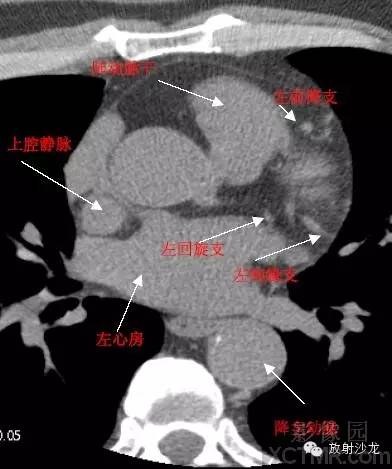

SVC –Superior Vena Cava上腔静脉

LMA -Left Main Artery冠状动脉左主干

LAD -Left Anterior Descending Artery左前降支

LCX -Left Circumflex Artery左回旋支

LMB -Left Obtuse Marginal Branch 左边缘支(钝缘支)